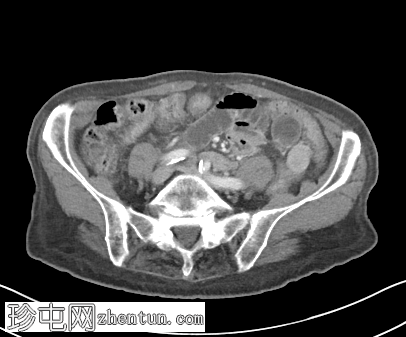

轴位增强扫描(门静脉期)

可见右侧股疝嵌顿,右侧股静脉受压,输出小肠袢塌陷,输入小肠袢扩张。可见中等量周围游离液体。无缺血征象。右侧努克氏管向内侧移位。疝颈位于腹壁下动脉起始部和腹股沟韧带下方。

肝脏可见多个小囊肿。左侧肾上腺肿大,内含低强化结节。

股总静脉受压、疝颈狭窄、女性、努克氏管向内侧移位、疝颈起源于腹壁下动脉起始部和腹股沟韧带下方等表现,更倾向于股疝而非腹股沟疝。